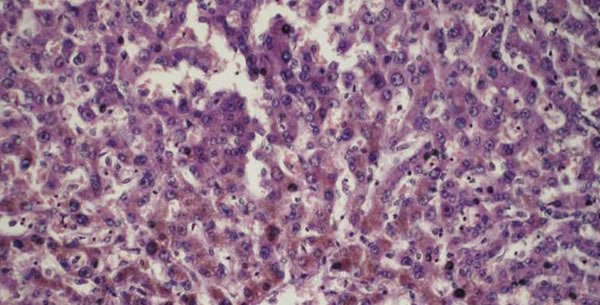

- Atrophia fusca: pojavljuje se kod ćelija nekih organa kao što su jetra, testisi, ganglijske ćelije, mikoard. Usljed nakupljanja u njima pigmenta lipofuscina ćelije su smedje boje.